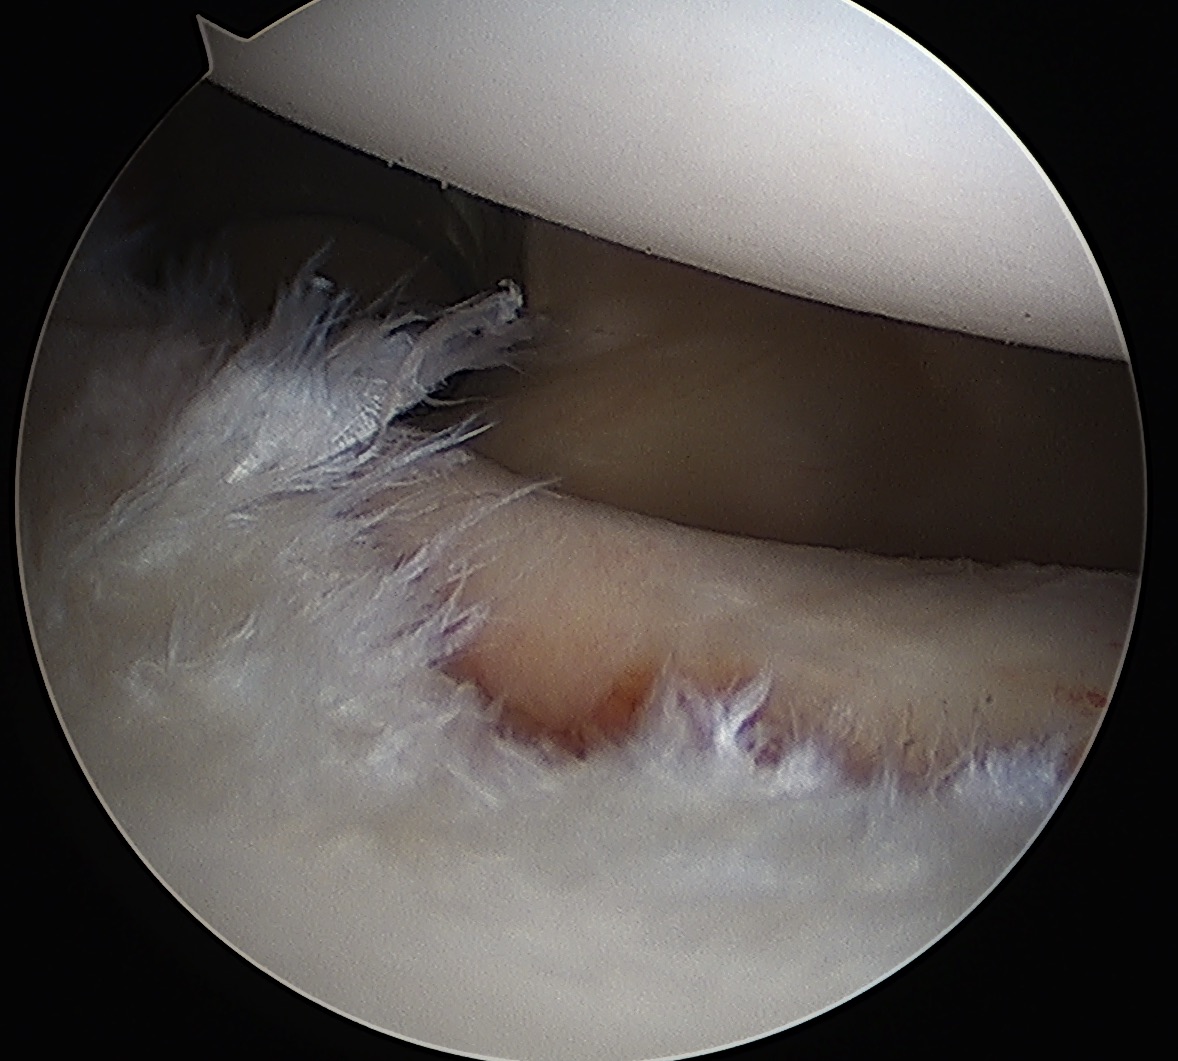

Mobilize labrum

Labral mobiliser / rasp

- labral tear can be obvious, but may have partially healed or healed medially

- change camera to anterosuperior portal for better view

- mobilize until can see subscapularis muscle underneath

- need to be able to advance labrum medially and superiorly for repair